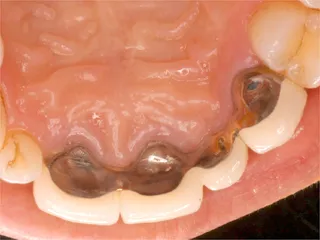

保険ブリッジ・頬側

■長所 ・安い ■短所 ・前後の歯を削り犠牲にする ※前後の歯を削り被せものをします ※抜けた歯のかわりに金属が付いています |